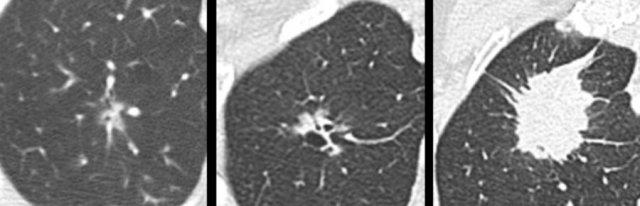

Ví dụ minh họa sự chuyển đổi từ hình thái kính mờ thuần túy (bảng trái) sang hình thái ung thư phổi dạng nang (bảng phải).

Ví dụ minh họa sự chuyển đổi từ hình thái dạng nang (bảng trái và giữa) sang hình thái ung thư phổi bán đặc (bảng phải).

Ví dụ này minh họa sự chuyển đổi từ hình thái bán đặc (bảng trái), sang hình thái dạng nang tạm thời (bảng giữa), rồi đến hình thái ung thư phổi đặc (bảng phải).